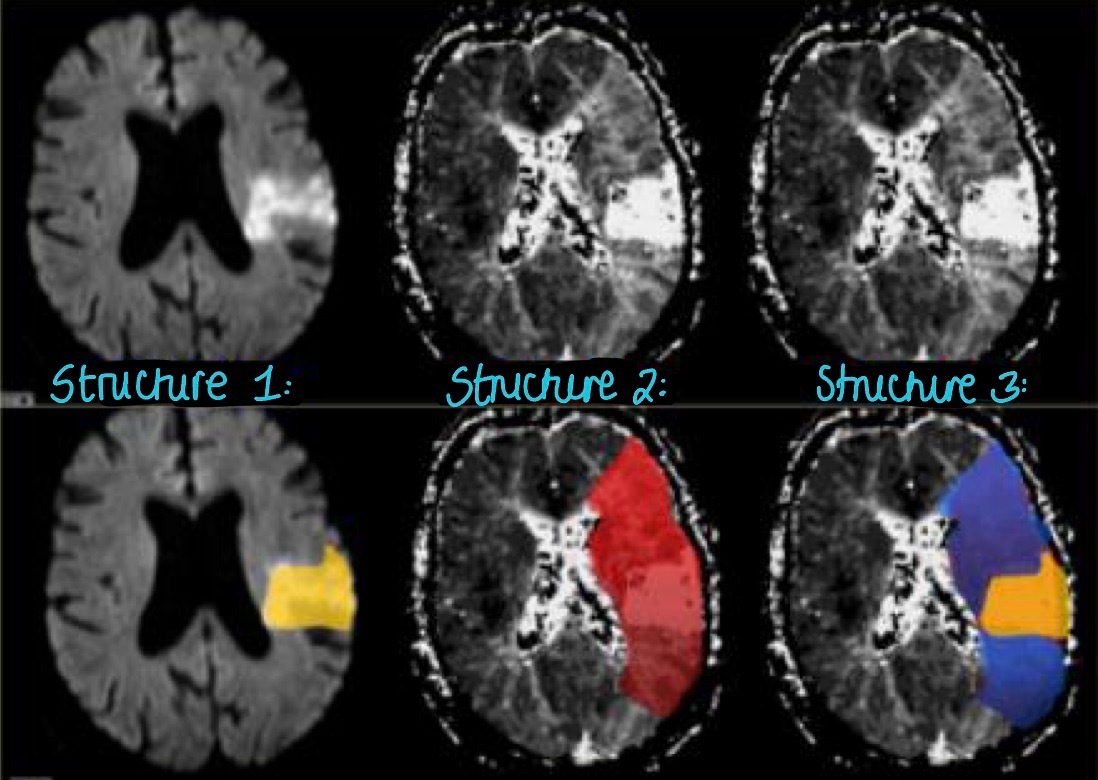

1. Label this image?

STRUCTURE 1:

- Diffusion

- the bright region indicates the area of low diffusion

- this is where we will see a stroke

STRUCTURE 2:

- Perfusion

STRUCTURE 3:

- this is a combination area of perfusion and diffusion

- this is where the stroke is occurring